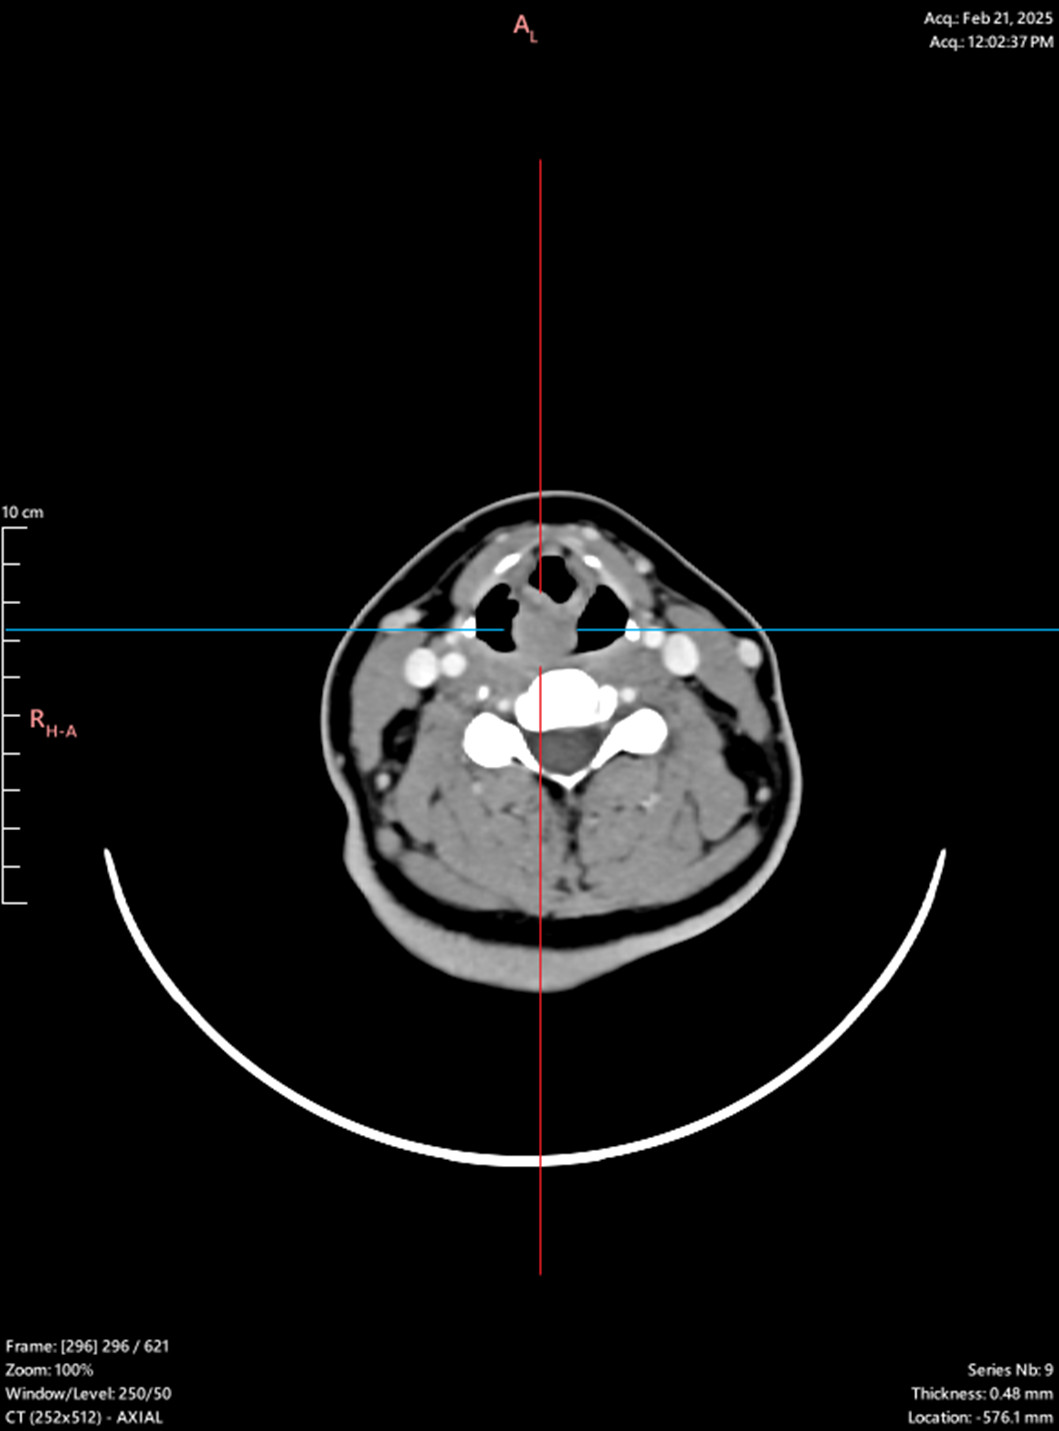

Patient No 2.

Laryngeal tumor - posterior commissure

Biopsy, granular cell tumor, granular cell myoblastoma, Abrikossoff tumor/div>

Symptoms: hoarseness, sensation of a foreign body in the throat, dysphagia